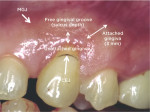

In Class I and Class II recession, there is no loss of interdental bone or soft tissue, and complete root coverage is expected. The difference between these two classes is the presence or absence of attached gingiva (Figure 1). Class I recession was originally described as recession that does not extend to the MGJ. While this is true, the distinction between attached and unattached gingiva was not emphasized. If gingiva was present on the facial, it was considered a Class I recession. In reality, if the gingiva is unattached, there is "hidden recession," and this is actually a Class II recession (Figure 2).11 Therefore, in sites where gingiva is present on the facial, it is necessary to probe to determine whether the gingiva is attached or unattached.

While complete root coverage is attainable in both Class I and Class II recession, different treatment modalities may be indicated. For example, if adequate keratinized tissue is present in a Class I recession, the simplest root coverage procedure, CPF, may be indicated, whereas in a Class II recession some type of soft-tissue grafting would be required. The CPF often can be done in a Class I recession but not in a Class II. Treatment of a Class II recession requires more complicated grafting procedures. Combining Class I and Class II into a single classification could be detrimental to the understanding of the clinician attempting root coverage. In the author's view, a new classification of recession presented at the 2017 World Workshop on the Classification of Periodontal and Peri-Implant Diseases and Conditions12 that combines Class I and Class II did not take this into consideration.